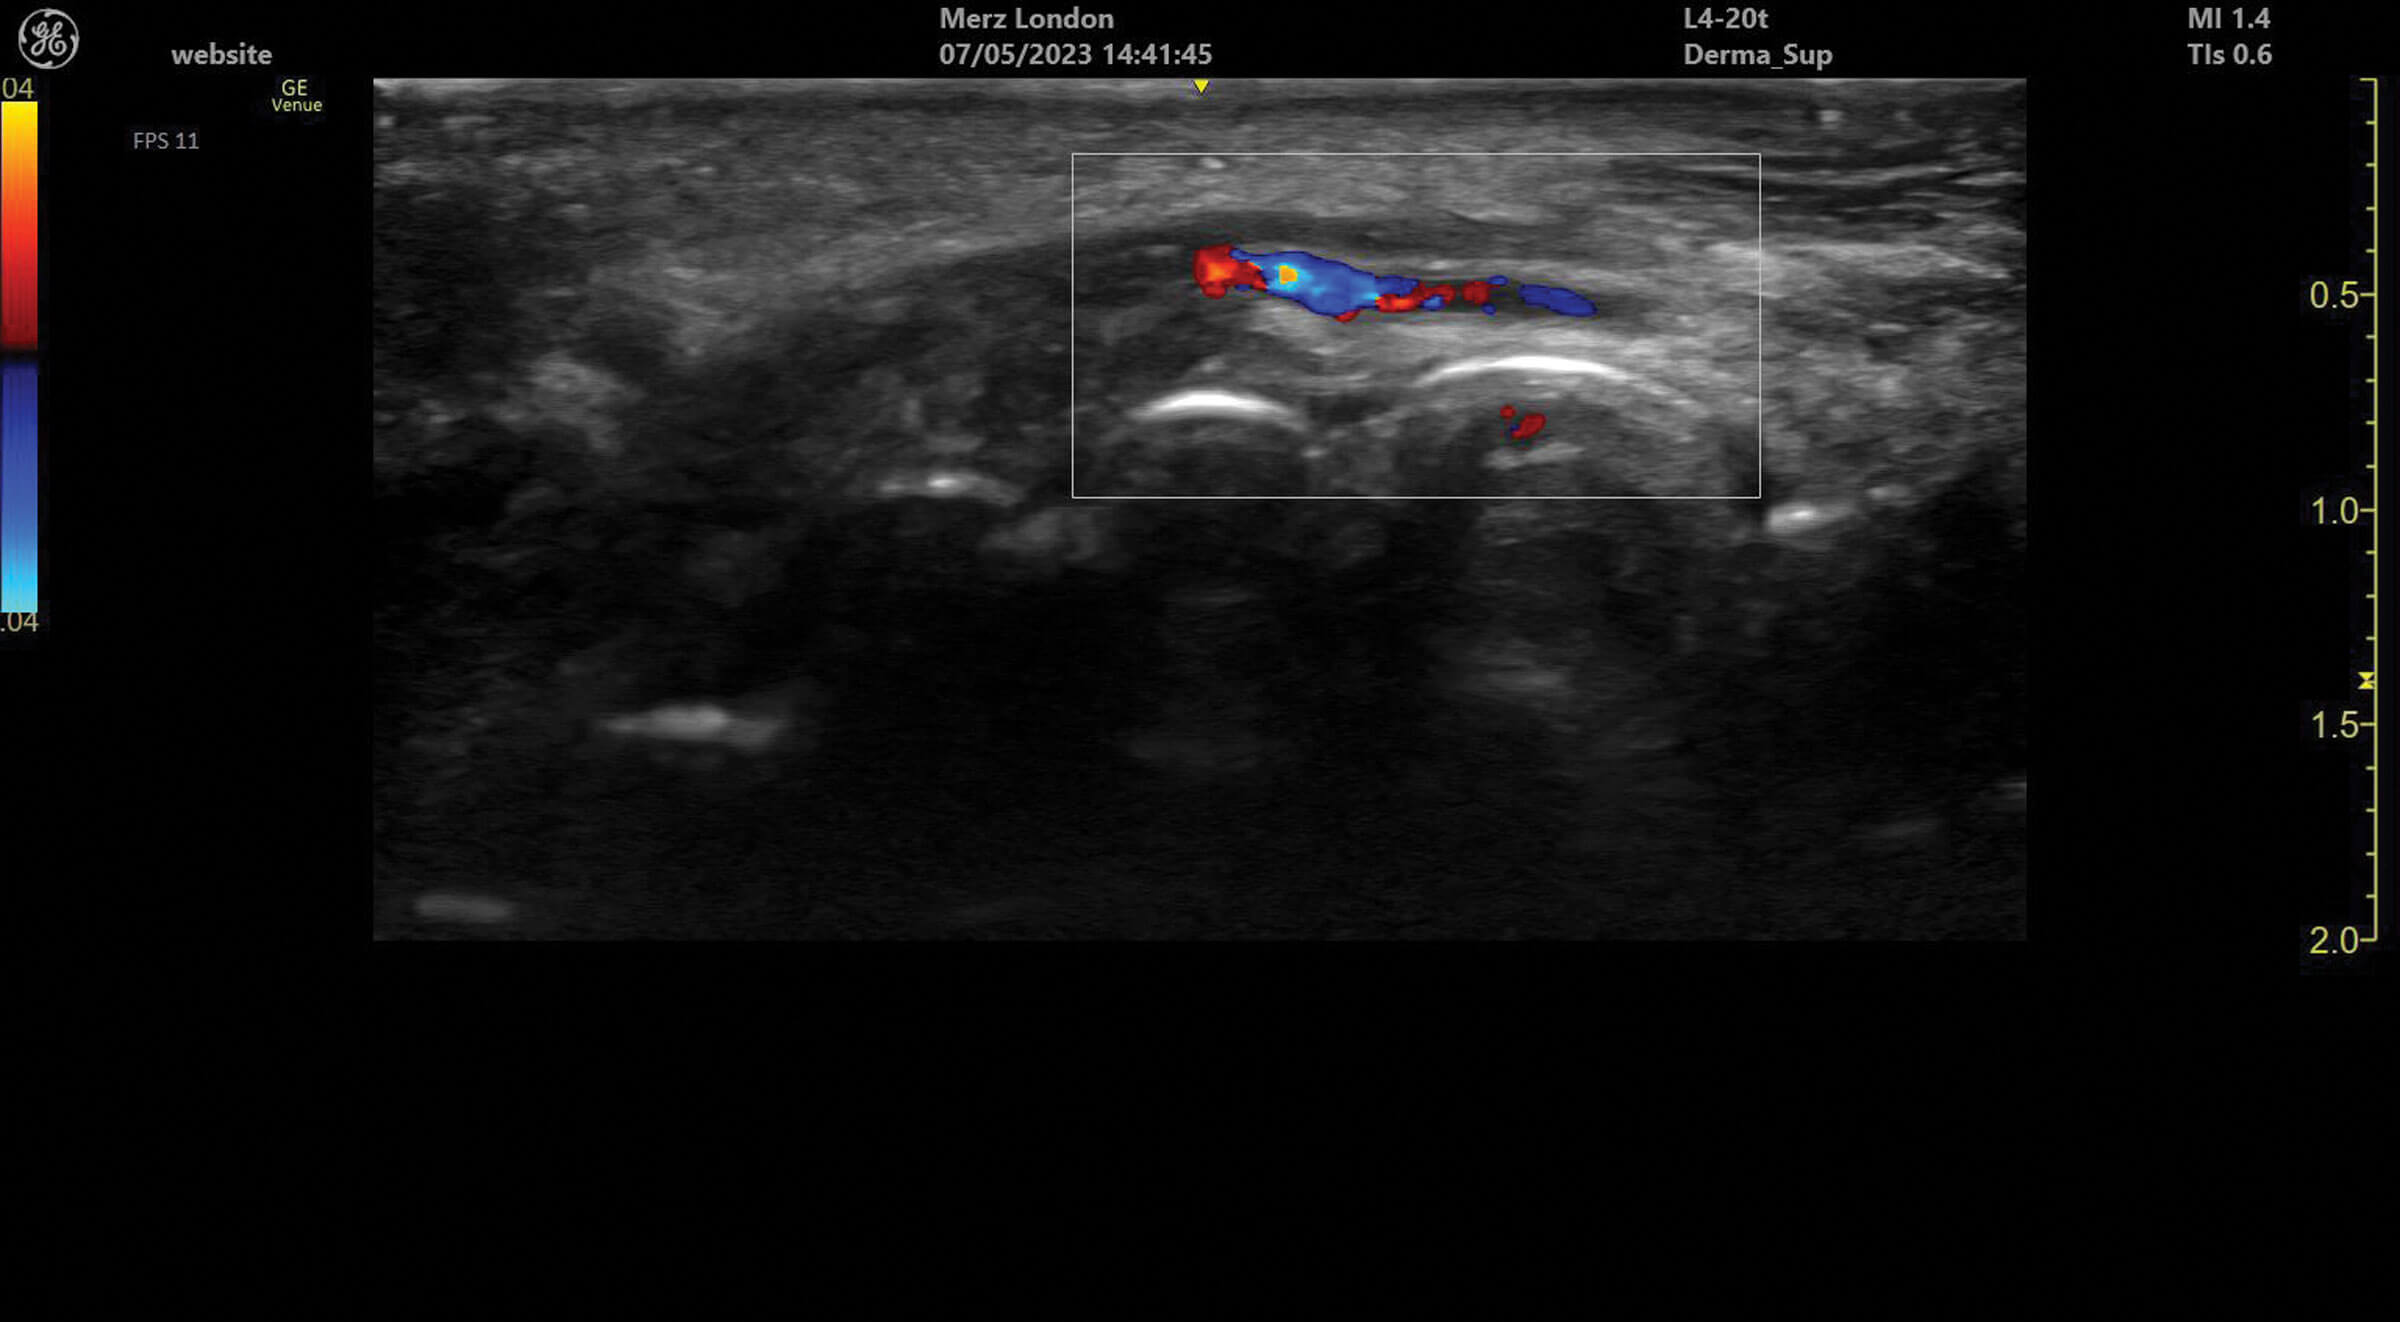

Figure 2: The superior labial artery running under the orbicularis oris muscle in the upper lip.

Ultrasound doppler can be used to assess blood vessel flow prior to treatments but can also help identify abnormalities in blood supply after filler treatment. Vessels can be identified and tracked in the tissue allowing for the observation of any anatomical variation. Blood vessels always appear as anechoic structures on ultrasound but, when using a colour doppler, flow can be detected either towards (red) or away (blue) from the ultrasound probe [1].